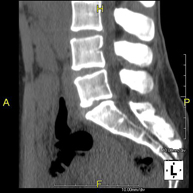

- TC Columna lumbar Prova radiològica que consisteix en obtenir imatges de les vèrtebres lumbars d'alta definició anatòmica, mitjançant l'ús d'un equip de TC (Tomografia Computaritzada). Indicacions: dolor lumbar sense / amb irradiació a les cames, dificultat per caminar, traumatisme. Prova radiològica que consisteix en obtenir imatges de les vèrtebres lumbars d'alta definició anatòmica, mitjançant l'ús d'un equip de TC (Tomografia Computaritzada). Indicacions: dolor lumbar sense / amb irradiació a les cames, dificultat per caminar, traumatisme.